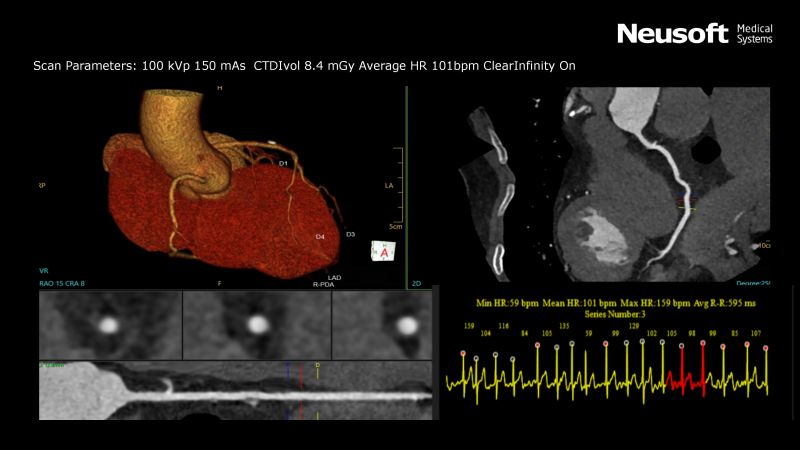

After applying our latest version of CMC algorithm, we observed a significant improvement in image quality of the coronary artery compared to standard cardiac reconstructions. The image below depicts a middle-aged patient who was admitted with chest pain and shortness of breath and underwent a Cardiac CTA Scan on NeuViz Epoch that imaged the entire heart in one cardiac cycle for coronary artery evaluation (Average HR: 101 bpm). The right coronary artery appeared continuous and had excellent visualization throughout the scan after using one-click CMC processing. The radiation dose delivered during the CTA procedure was reported as low as 8.4 CTDI due to our introduction of AI-based Deep Learning Reconstruction technology, ClearInfinity, while maintaining image quality.